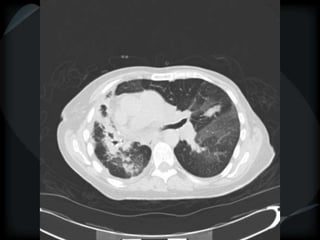

Airspace Patterns

 Inter and intralobular septal thickening / ground glass/crazy paving

Crazy paving